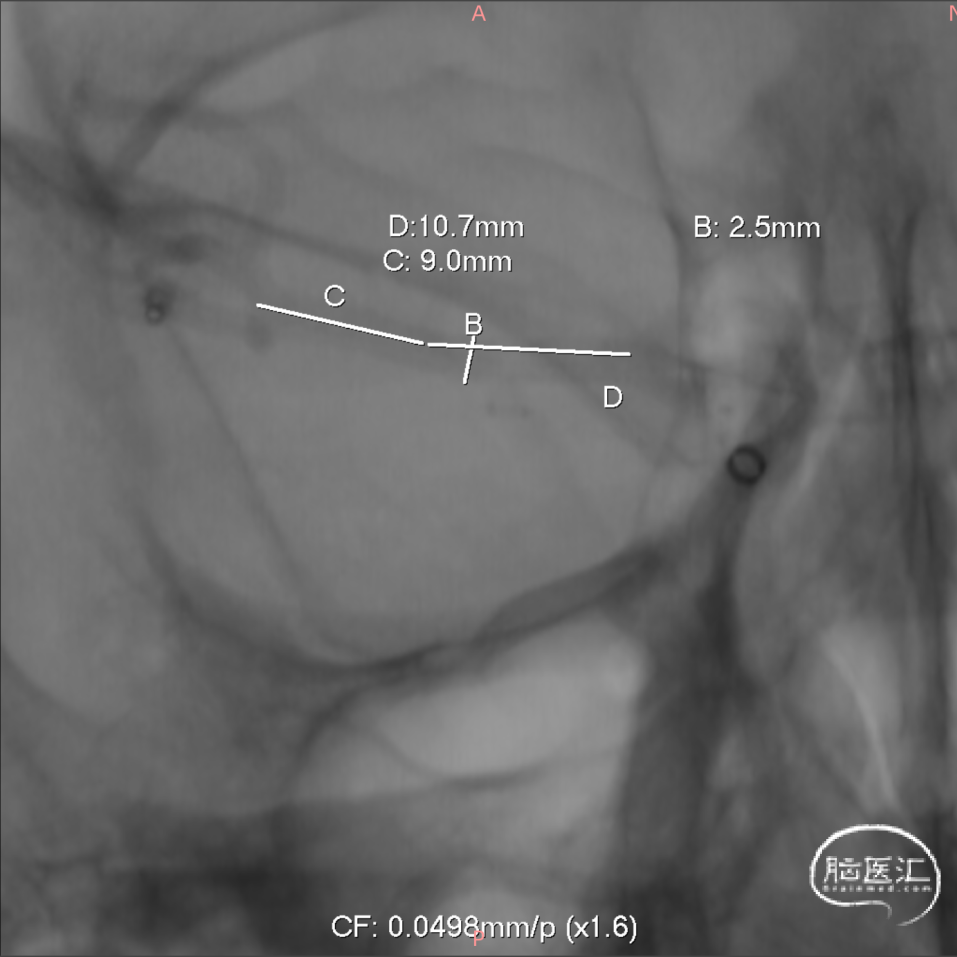

支架选择:

测量血管远端1.5mm,近端2.5mm,支架直径选择3.25mm,因为该部位有豆纹动脉发出,故考虑选择一枚短支架(15mm),尾端置于大脑中动脉M1段远端1/3。

密网支架:FD Surpass Evolve 3.25mm*15mm